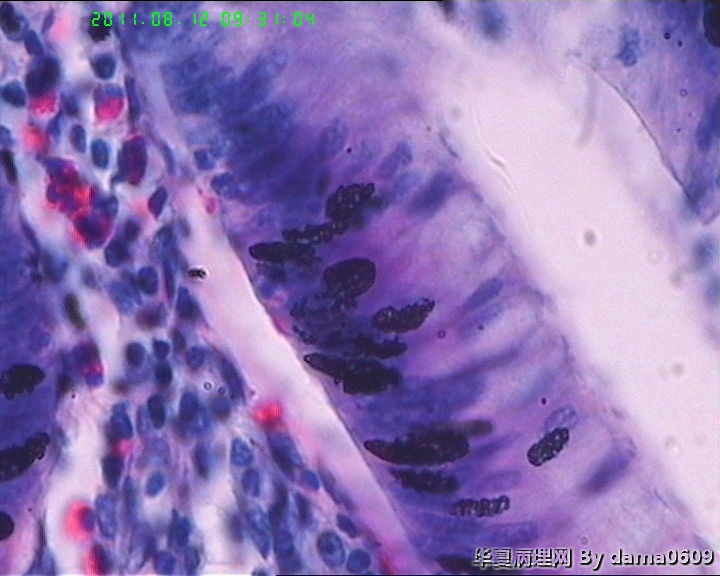

老师好!以前学生也遇到过此情况,偶尔染出的片子的细胞核的上方会出现黑色的异物,多见于子宫平滑肌瘤的片子。很影响观察核的形态、核分裂像。初以为是苏木素杂质,而且不经常出现,所以没在意。最近此现象很严重,许多的片子都出现此情况,反复过滤苏木素不见好转,新配苏木素也是如此。经过仔细观察,现发现似乎不是杂质,是细胞核上方覆盖着小气泡(如图),不知何故,如何解决??另外一个问题,我们的片子封片后经常出现斑片状或整张片子模糊,似乎树胶没有封到(如图),不只是脱蜡不干净,还是脱水出问题?此想象并不是出现在所有的一批片子上,而是个别。请老师们帮助指点。谢谢。